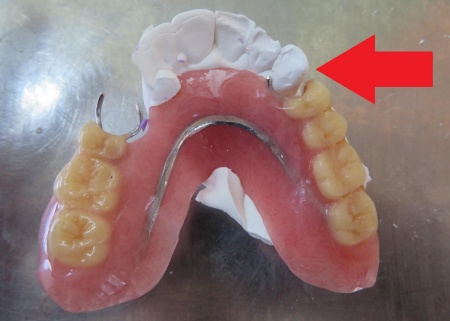

続いて、模型上の歯に合わせ、金属ワイヤーを1本ずつ手で曲げながら形を整えて新しいクラスプを製作します。

その後、完成したクラスプを既存の入れ歯に組み込み、入れ歯がしっかり歯にかかるよう慎重に調整しました。

最後に入れ歯を装着し、安定して使用できるか、痛みや違和感がないか、見た目や噛み合わせに問題がないかを確認し、治療を終了しています。